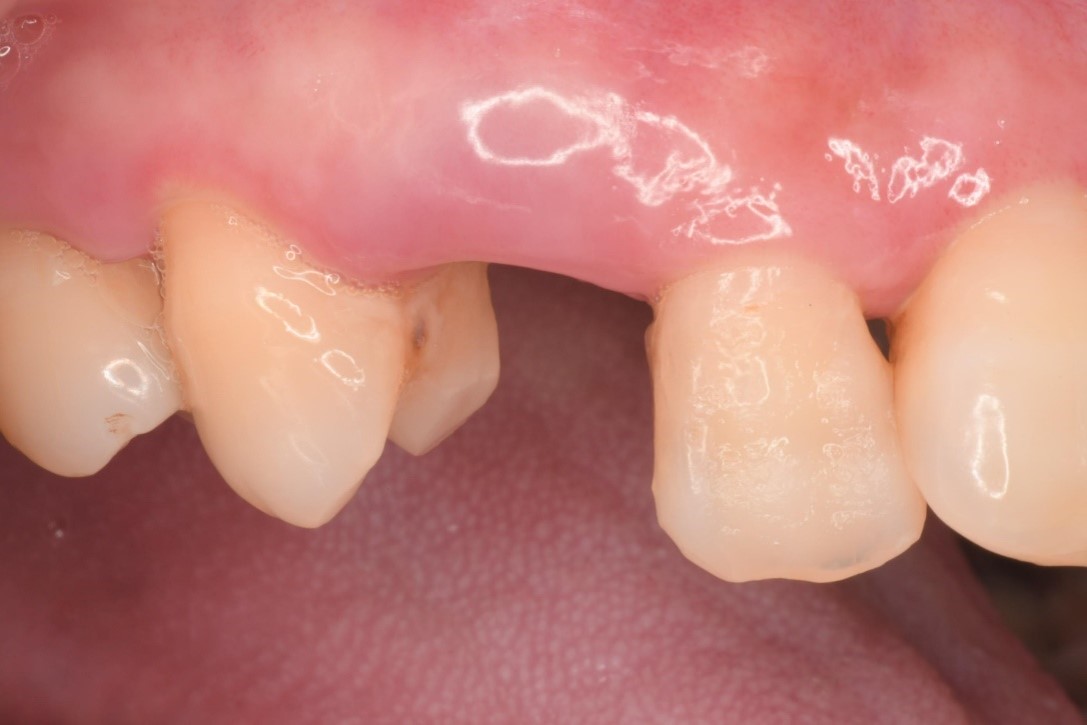

前牙修復及立即植牙-蛀牙-#13-23

人工植牙

前牙美學

立即植牙-前牙